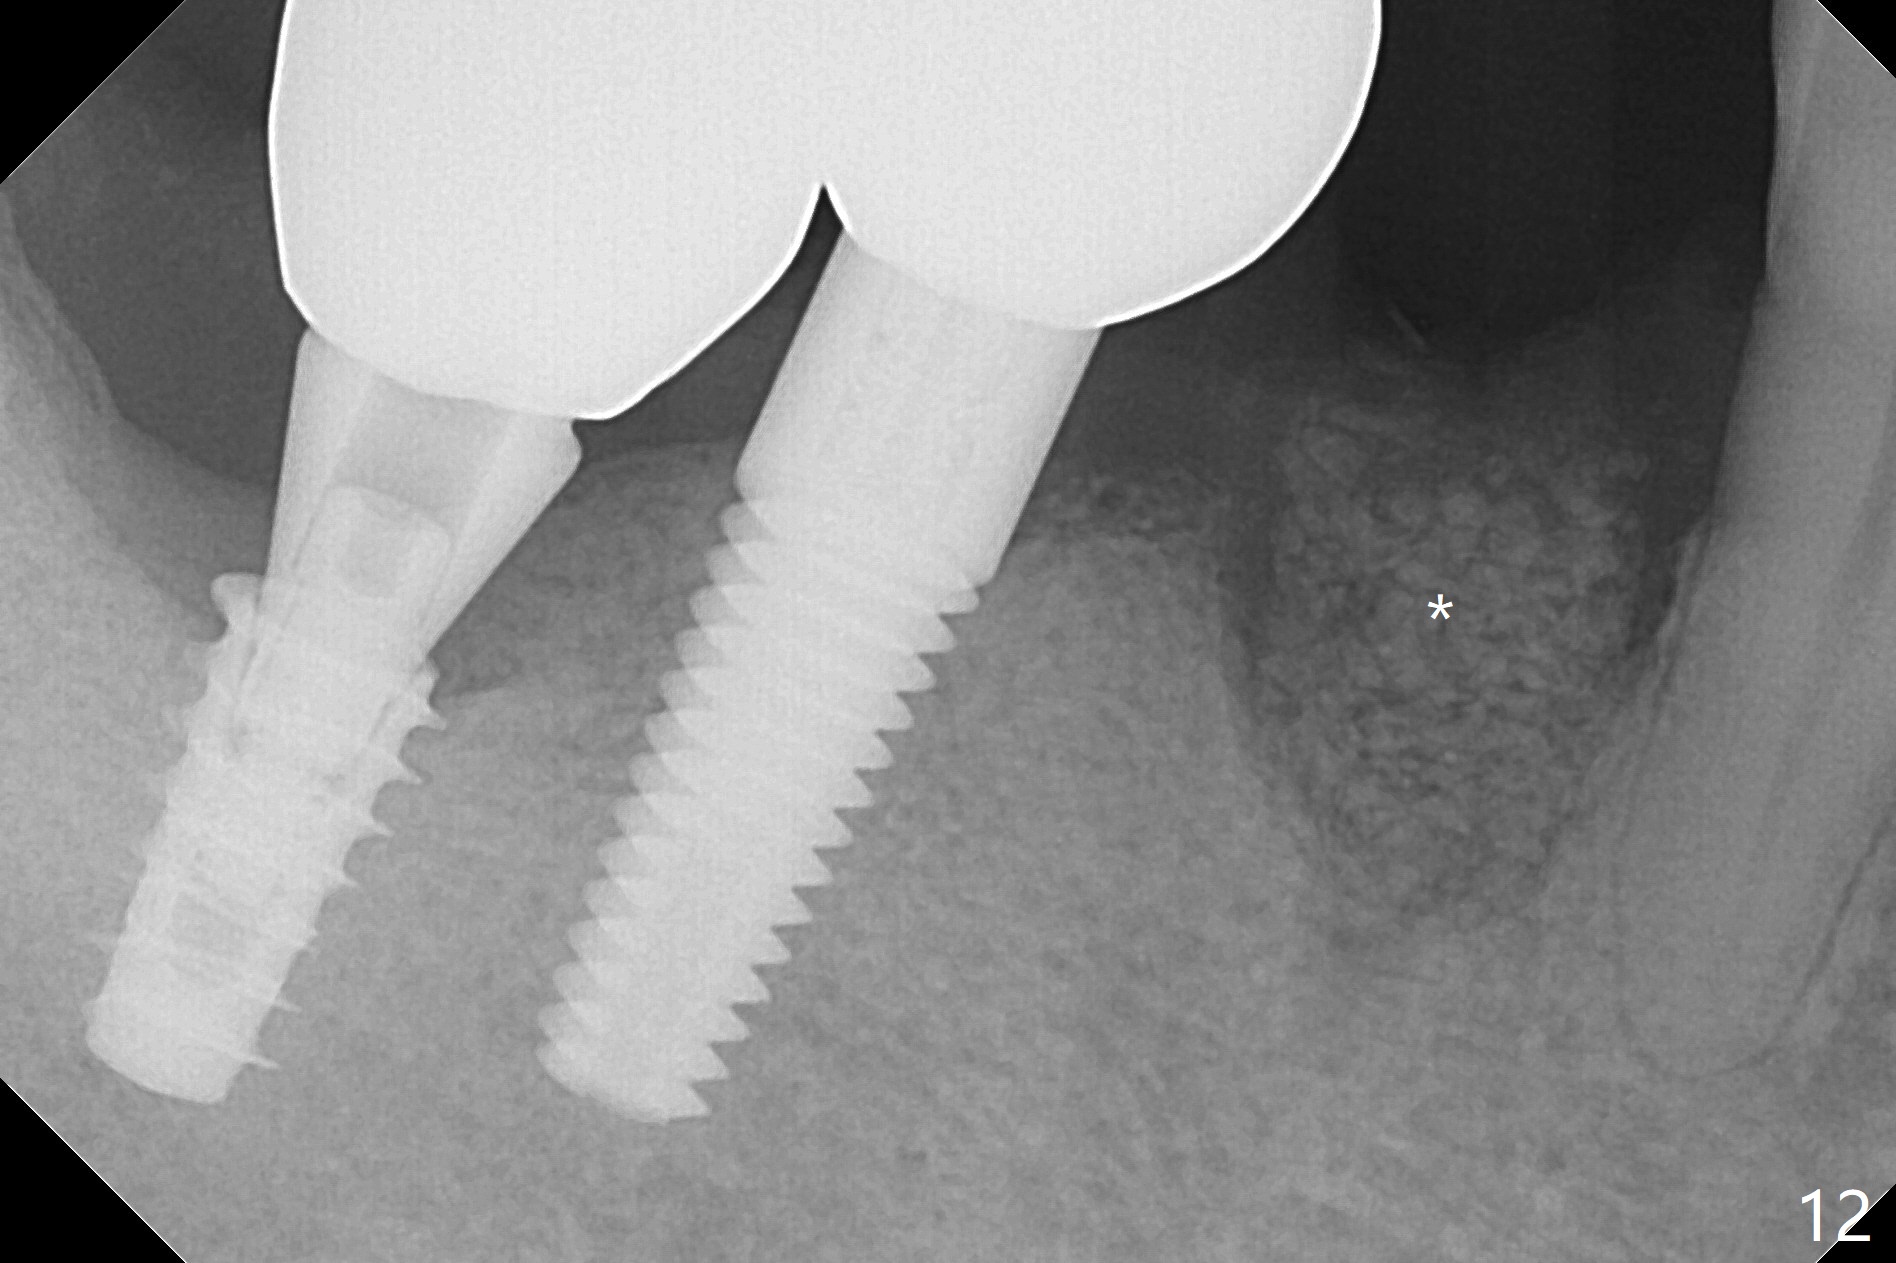

The affected tooth (#28) has buccal gingival recession (Fig.1). As expected, the buccal plate is found low after extraction. Osteotomy is established in the lingual slope of the socket with 1.5 mm drill for 13 mm (Fig.2,3). Following use of Magic Drill 3.3 mm for 13 mm, a 4x11 mm dummy implant is incompletely seated (Fig.4); it is also close to the Mental Loop (Fig.4 red line). After use of Final Drill, a 4x9 mm IBS implant is placed 4 mm and 2 mm subgingival buccal and lingual, respectively (Fig.5) with a large buccal gap (Fig.6 (40 Ncm)). After placement of allograft in the peri-implant space (Fig.7 *), a 4.5x5.7(4) mm abutment is placed (A). A piece of gauze is placed in the remaining buccal space prior to provisional fabrication (Fig.8 *). The space occupied by the gauze is later filled with collagen plug before provisional seating. The gingiva is healthy around the provisional 12 days postop (Fig.9). To reduce buccal gingival recession, the buccal margin of the provisional is shortened 4.5 months postop (Fig.10 arrow). PA taken 5.5 months postop is shown with the implant at 31. The lingual gingiva is erythematous, edematous, and recessive with +BOP and deep pockets 14 months postop (Fig.11). It appears that the small and short implant is not favorable for healing. The infected implant is removed with the missing buccal plate; bone graft is placed 15 months postop (7 months post cementation, Fig.12,13).